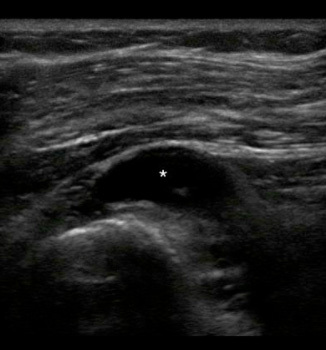

Knee Medial Meniscus Cyst Transverse Image

Asterisk: Cyst